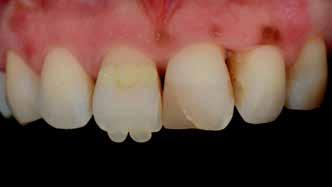

A 19 éves hölgypáciens azzal a kéréssel jelentkezett a rendelőnkbe, hogy szebb fogakat szeretne. Az első konzultáció alkalmával megkérdeztük, hogy mi zavarja leginkább a fogazatának jelenlegi megjelenésében, valamint azt is megbeszéltük vele, hogy milyen végeredmény elérése esetén lenne maradéktalanul elégedett. Ebben az esetben a kezelési célokat az alábbiakban határoztuk meg:

A páciens fogazata esztétikai megjelenésének és funkcionális működésének a lehető legtöbb, saját foganyag megtartása mellett történő helyreállítása (1. és 3. ábra).

A tényleges protetikai ellátás megkezdése előtt a páciens mosolygás közben látható fogait otthoni fogfehérítés keretei között a kérésének megfelelő A1-es fogszín eléréséig fehérítettük. A fehérítés során a későbbiekben héjakkal ellátásra kerülő fogak színén nem változtattunk. A fogak előkészítése részeként csupán a két felső nagymetsző (1.1,2.1) incizális élét kellett kismértékben redukálni. A többi felső front fog (1.3,1.2,2.2,2.3) nem került preparálásra.